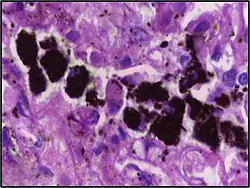

Alveolar macrophages are frequently seen to contain granules of exogenous material such as particulate carbon that they have picked up from respiratory surfaces. Such black granules may be especially common in smoker's lungs or long-term city dwellers.

Comparison of pigmented pulmonary macrophages

| Disease | Macrophage name | Macrophage pigment appearance (HE stain) | Usual macrophage location | Associated medical history | Image | Image comment |

| Anthracosis | Black-brown granules | Interstitium (perivascular) |

| Respiratory bronchiolitis | "Smoker’s macrophages" | Yellow to light brown and finely granular[4] | Airways (especially respiratory bronchioles) | Tobacco smoking |

Smoker's macrophage in center |